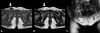

The processus vaginalis within the inguinal canal forms the canal of Nuck, which is a homolog of the processus vaginalis in women. Incomplete obliteration of the processus vaginalis causes indirect inguinal hernia or hydrocele of the canal of Nuck, a very rare condition in women. Here, we report 2 cases of hydrocele of the canal of Nuck that were diagnosed with ultrasonography in both cases and magnetic resonance imaging in 1 case to confirm the sonographic diagnosis. High ligation and hydrocelectomy were conducted in both patients. In 1 patient, 14 months later, the occurrence of contralateral inguinal hernia was suspected, but did not require surgery. The other patient had a history of surgery for left inguinal hernia 11 months before the occurrence of right hydrocele of the canal of Nuck. In both cases, the occurrence of an inguinal hernia on the contralateral side was noted.